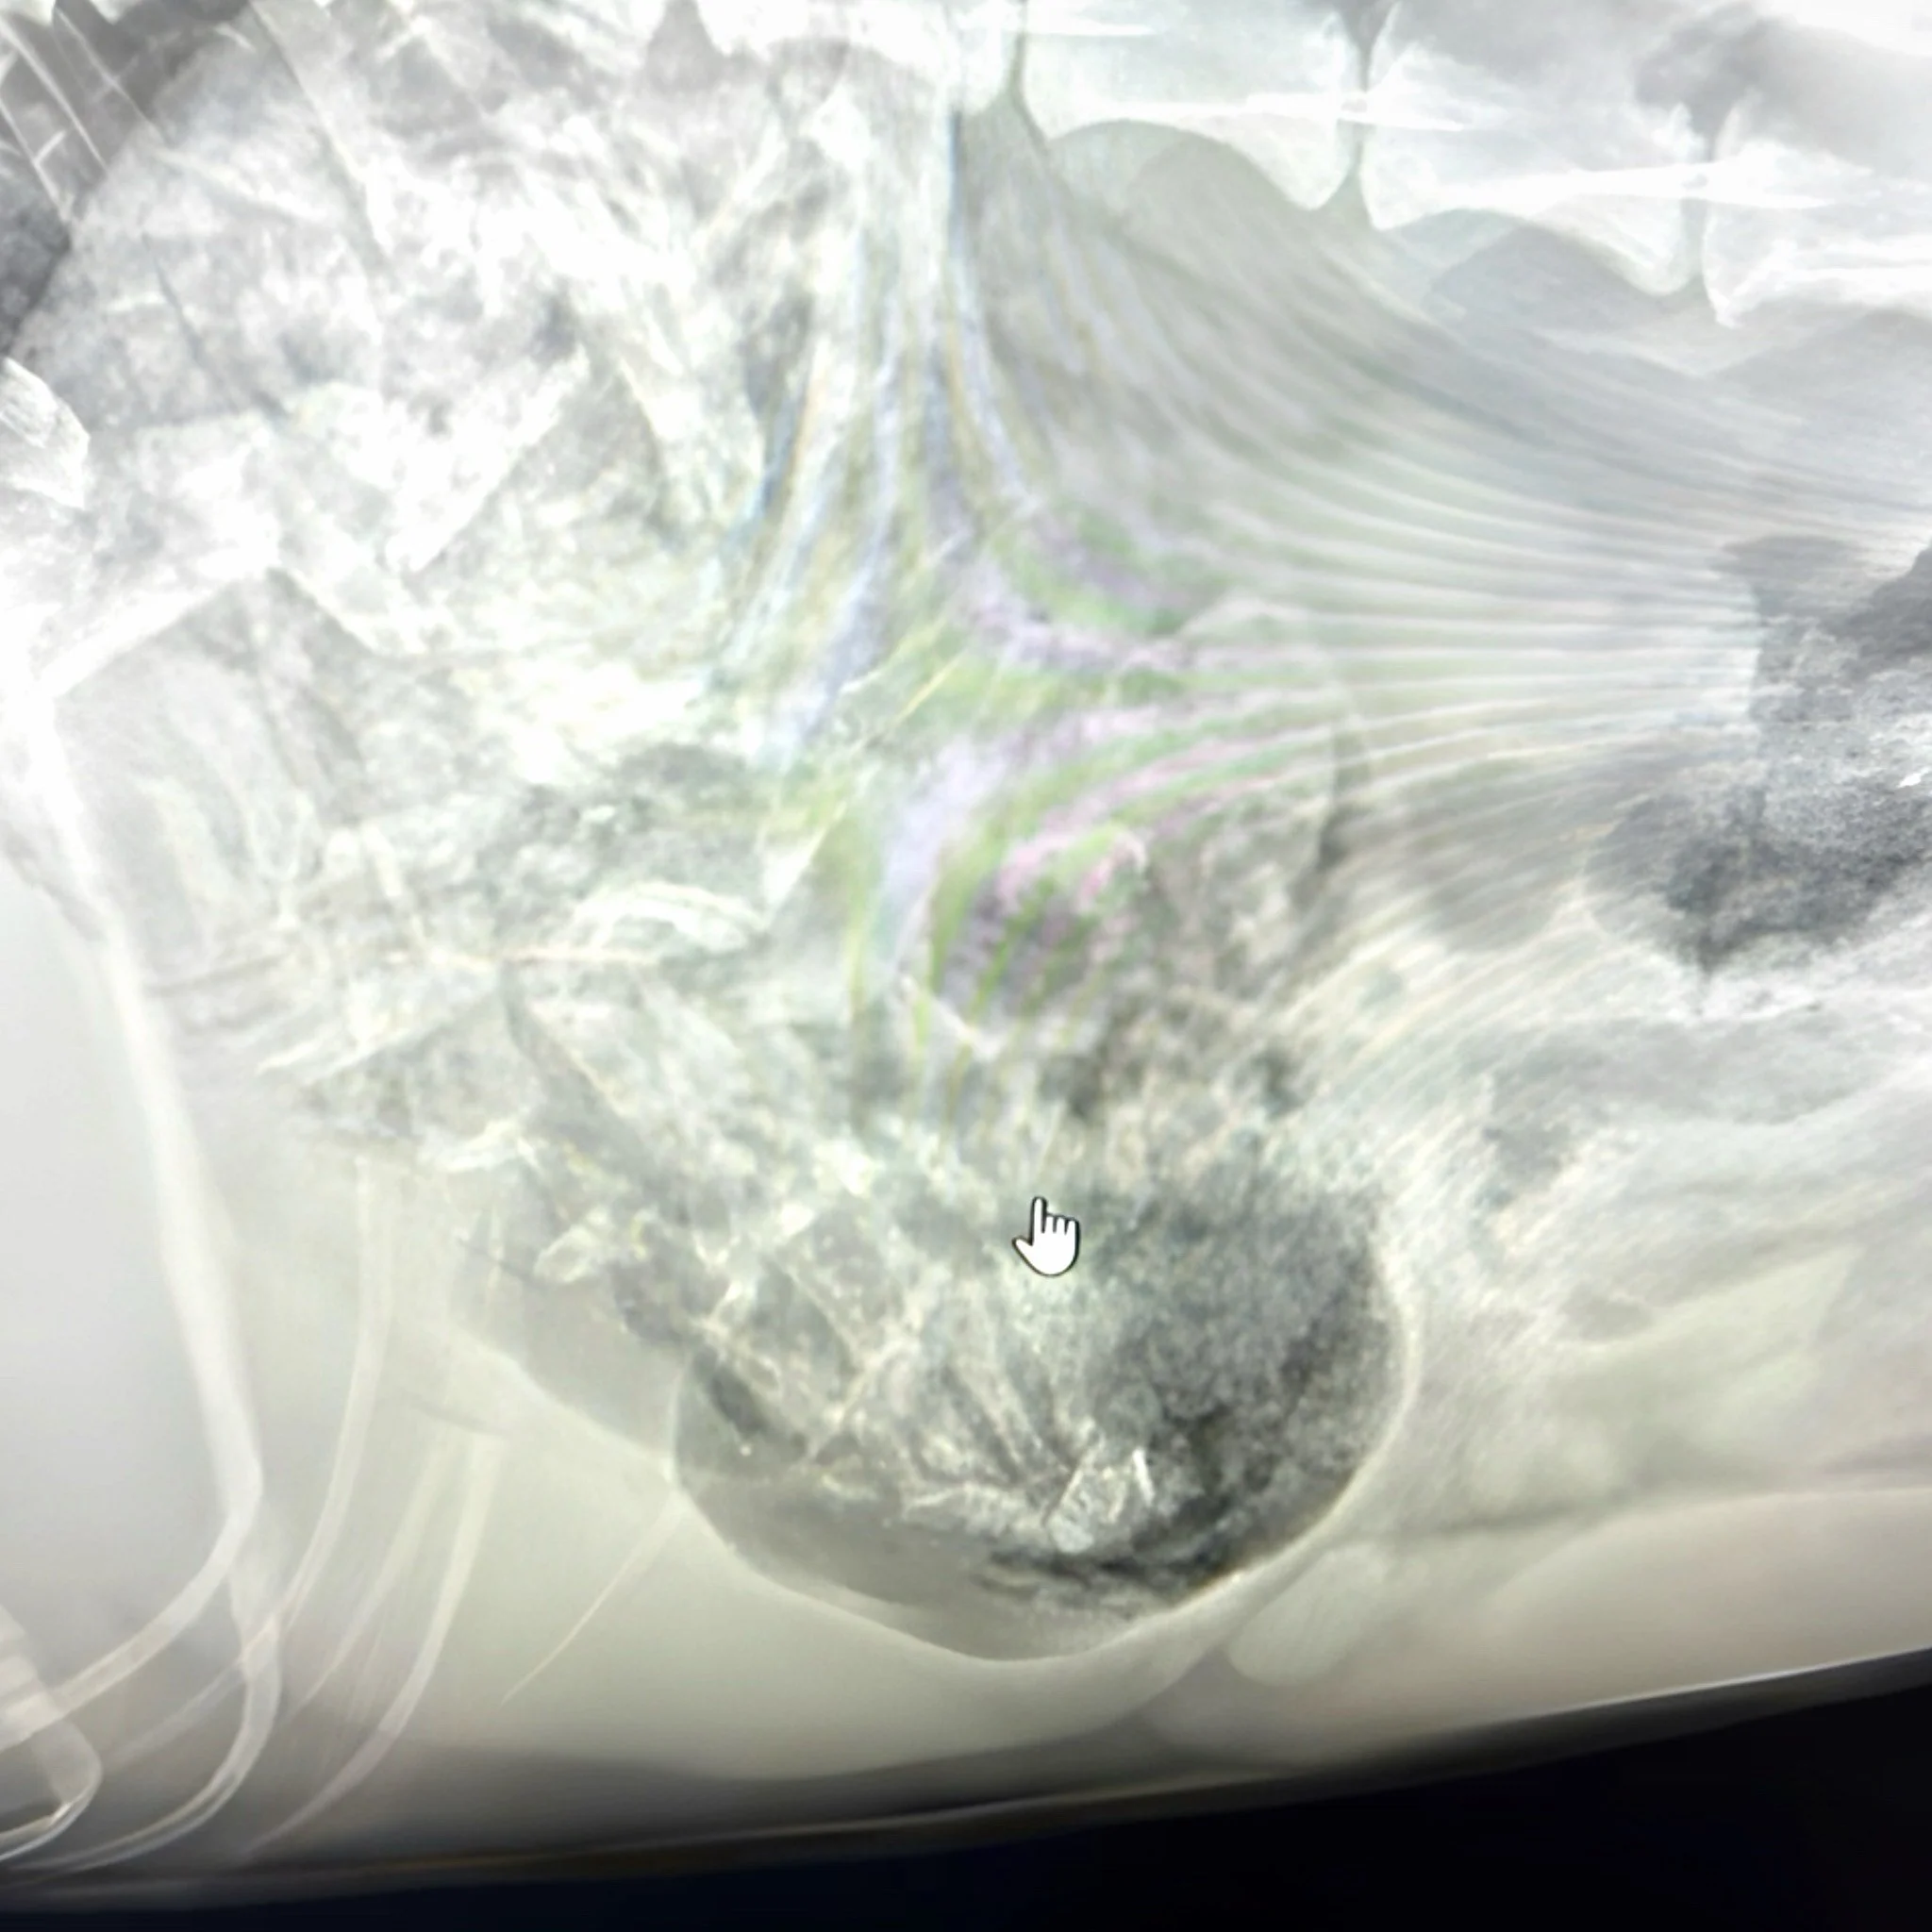

By evening, poor Izzie felt quite ill. At Omokoroa Pet Vets, the kindly doctors took an x-ray of her tummy. The whole room gasped! For there, glowing on the screen, was the unmistakable bony wave from a possum paw.

It wasn’t going to pass on it’s own. Izzie needed emergency surgery. That very night, brave Dr Nick and Dr Raewyn worked under the bright theatre lights. With careful hands, they opened Izzie’s tummy and removed the grizzly prize. Out came fur, muscle, tendons and bones until the sharp little claw, still reaching as though it meant to grab something. Instead of discarding it, the vets preserved it in formaline and placed it high upon their “Shelf of Oddities,” where strange and curious finds from previous patients were displayed.